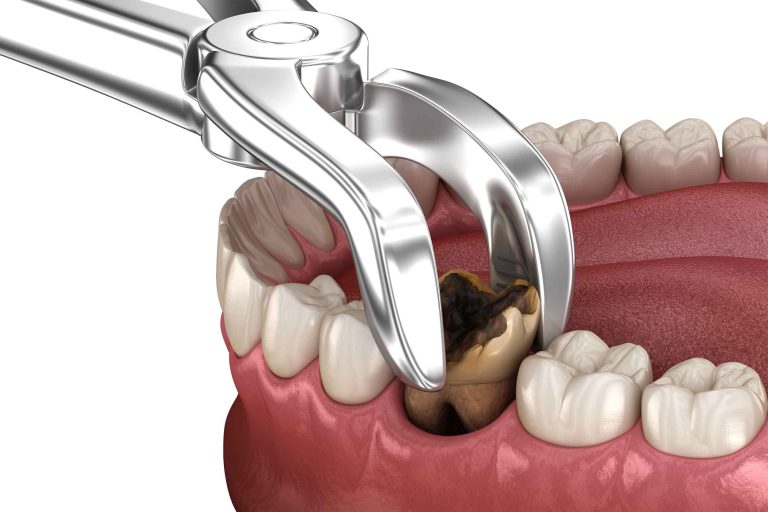

Bila fikir tentang cabutan gigi, mesti anda akan fikir punca gigi kena cabut adalah disebabkan gigi rosak atau gigi yang goyang akibat usia. Sebenarnya, doktor akan mengesyorkan agar pesakit menjalani prosedur cabut gigi apabila kesihatan gigi telah terjejas yang tidak dapat dibaiki lagi.

- Gigi Rosak atau Berlubang – Gigi berlubang biasanya boleh ditampal. Tetapi apabila lubang semakin dalam dan bakteria sudah sampai ke akar gigi, ia mengakibatkan jangkitan pada saluran akar gigi. Jika lambat buat rawatan, gigi akan semakin rosak. Jika kerosakan gigi telah menjadi sangat teruk sehingga gigi tidak dapat diselamatkan, doktor mungkin mengesyorkan cabutan gigi.